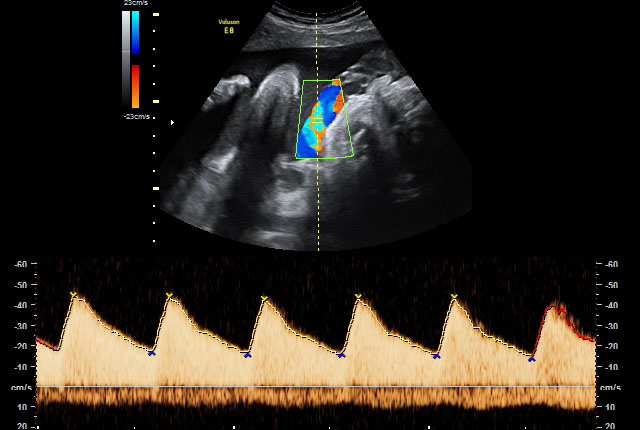

Wenn der Verdacht auf fetale Wachstumsstörungen und/oder fetale Fehlbildungen besteht, wird die Versorgungssituation des Ungeborenen durch eine spezielle dopplersonografische Untersuchung überwacht und die Funktion der Plazenta überprüft. Wir setzen hierbei den hochauflösenden Farbdoppler, also die sogenannte farbkodierte Doppler-Sonografie ein.

Bei der farbkodierten Doppler-Sonografie, einer bestimmten Form der Ultraschalluntersuchung, wird die Richtung des Blutflusses farblich dargestellt, um den Blutfluss in Arterien von dem in Venen unterscheiden zu können. Damit können auch Aussagen über das Ausmaß eventuell vorhandener Durchblutungsstörungen getroffen werden.